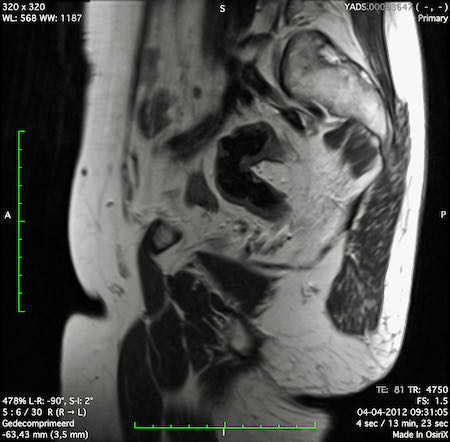

Hình ảnh

Các hình ảnh được cung cấp cho thấy ung thư biểu mô tế bào nhẫn với tình trạng dày lan tỏa thành trực tràng, hình ảnh bia bắn điển hình, và sự xâm lấn mỡ mạc treo trực tràng.